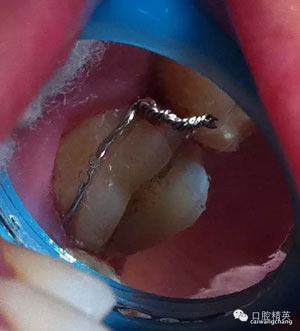

上圖可見該患者的牙斜向裂開,同時沒有做完善的根管治療

先給與根管充填(前提是無根管劈裂),牙膠截斷于根管口

頰部預(yù)備溝槽,準備結(jié)扎絲復(fù)位,現(xiàn)已改為成型夾或血管鉗鉗夾復(fù)位